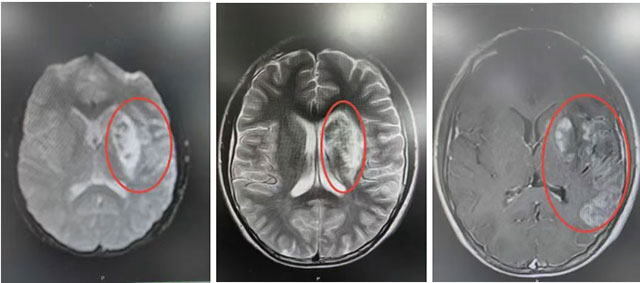

家属情急之下将其转至西南医科大学附属中医医院。入院后医生查看患者后,考虑为急性脑梗死、基底动脉尖综合征,随即与患者家属沟通病情,立即予以气管插管、有创呼吸机辅助通气,患者病情稳定后,医护团队立即启动针对性治疗,全力遏制病情进展。

急诊铃再次划破寂静,一位由合江县转诊的急性左侧颈内动脉闭塞的患者被紧急送来,时间紧迫、病情凶险,若不及时干预,可能导致不可逆的神经功能损伤。医护团队立即启动急诊流程,快速完善检查、评估病情,与家属沟通后,紧急开展救治,急诊全麻下行左侧颈内动脉开通术,整个诊室、手术室灯火通明,医护人员的身影在各个区域穿梭。